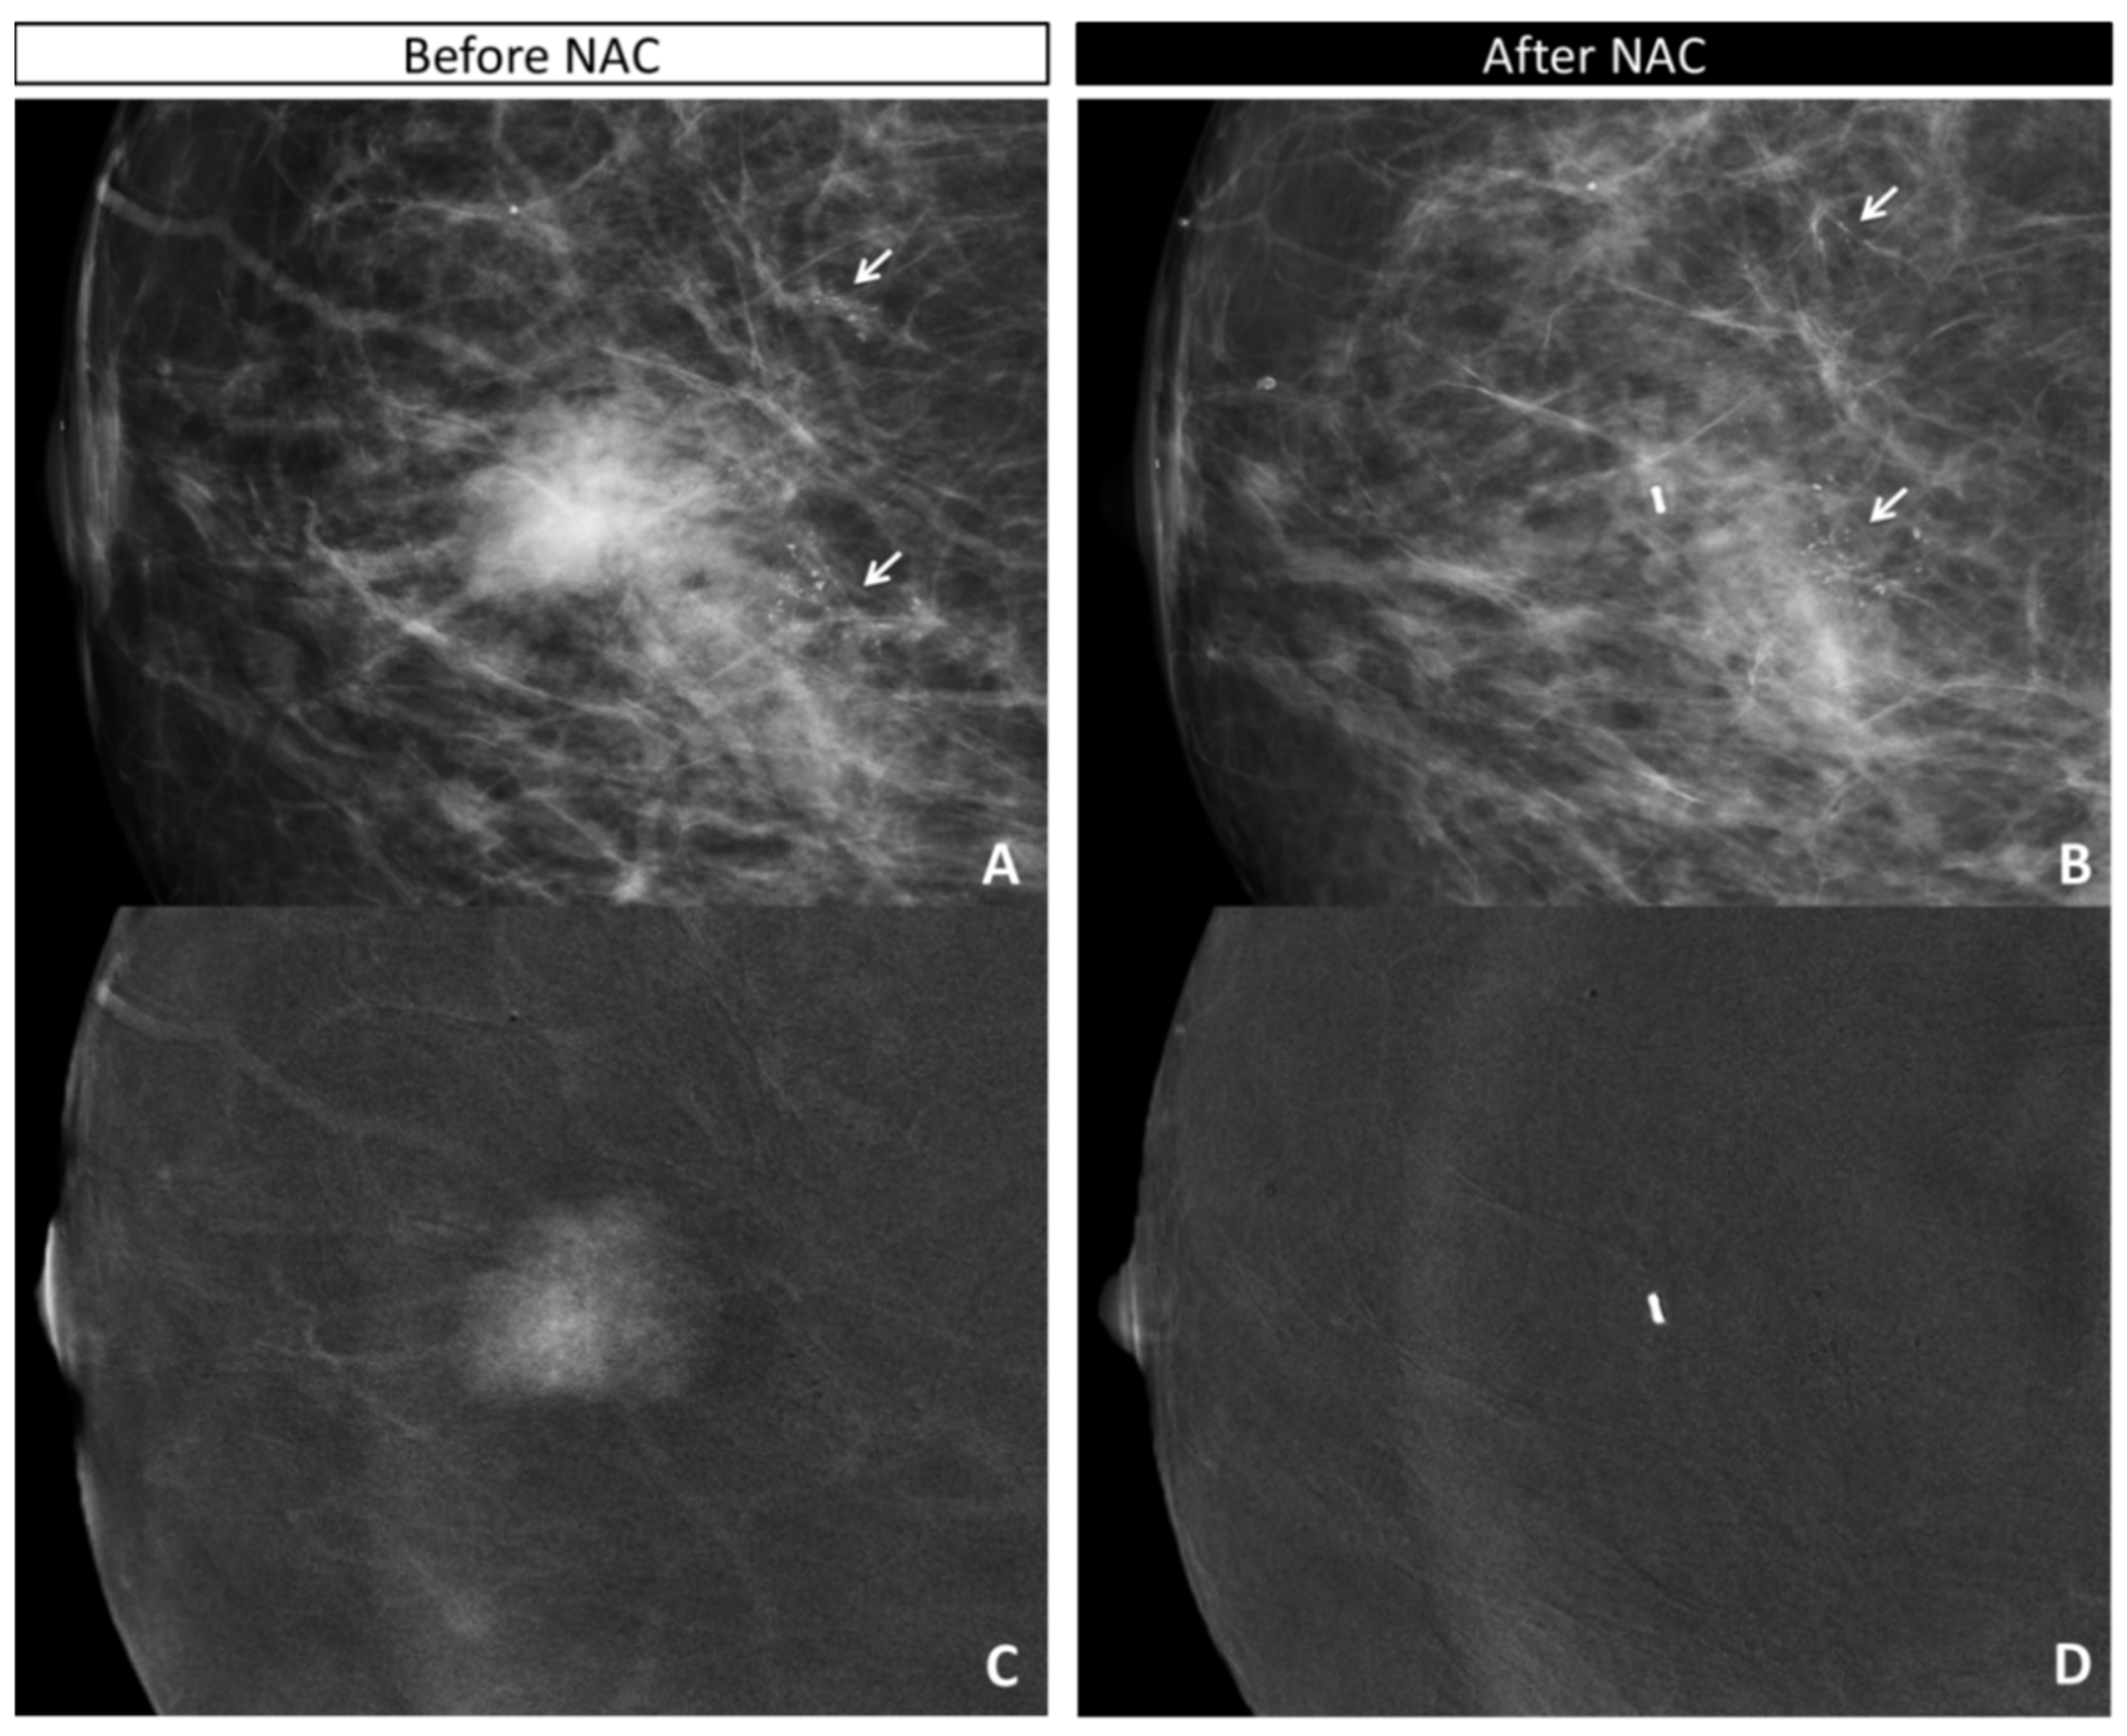

2.4. CEM Image Acquisition and Retrospective Review

- the absence or presence of contrast enhancement (CE) on recombined images, defining the maximum dimension (mm) of CE before NAC (defining the tumor bed) and after NAC (defining the residual disease);

- the maximum extension (mm) and characteristics (according to BIRADS lexicon) of calcifications on low-energy images before NAC (defining the tumor bed) and after NAC (defining the residual disease);

- the maximum extension (mm) of the combined evaluation of pathological calcifications and enhancement before (defining the tumor bed) and after (defining the residual disease) NAC;

3.3. Analysis of Discordant Cases

3.4. Concordance Between CEM and Pathology in the Measurement of Residual Tumor Size